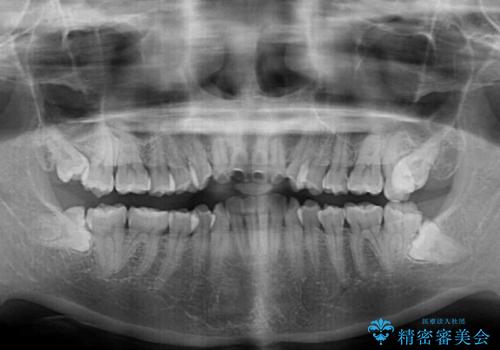

- 前歯のデコボコや口元の突出感、口の閉じにくさを気にして来院された患者様です。

上下左右第一小臼歯4本を抜歯し、ワイヤー装置にてデコボコを解消しながら口元を引っ込めるよう矯正治療を行うこととしました。

抜歯スペースを閉じている過程で、左側の上下犬歯が引っかかってしまい、進捗が停滞しましたが、当初予定の2年~2年半の間で無事に治療を終えることができました。